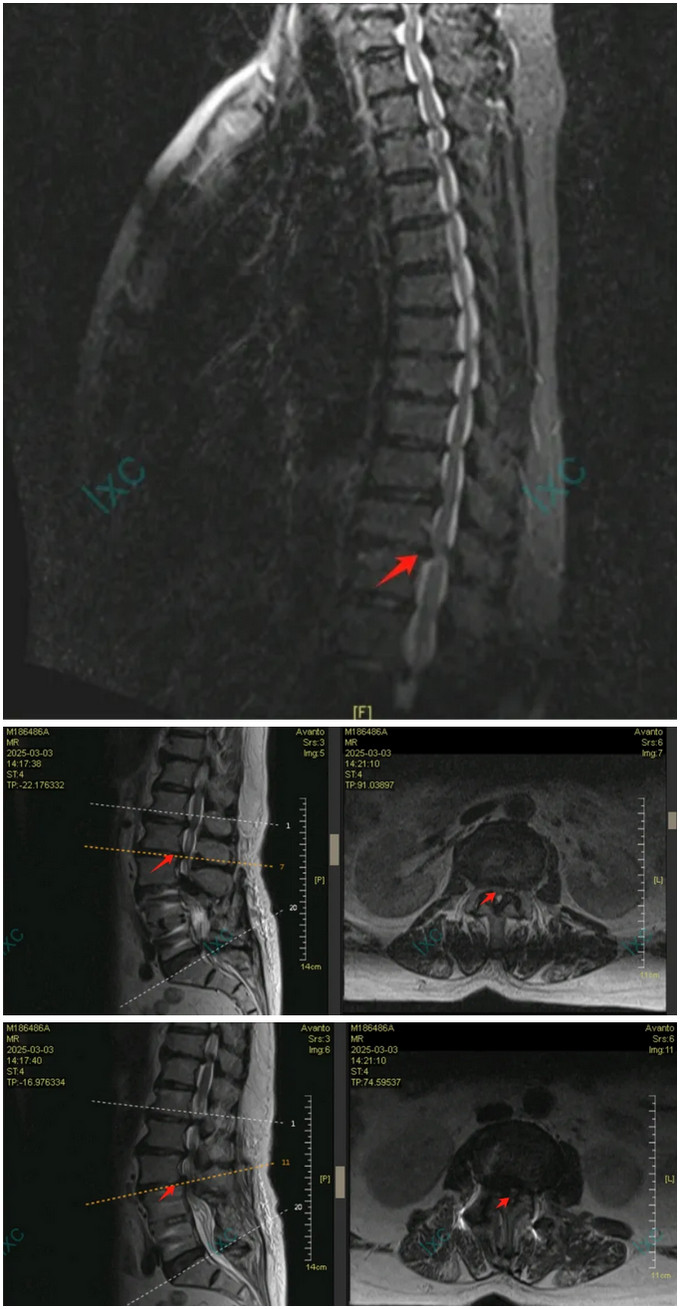

(胸椎MR顯示T11-12節(jié)段脊髓壓迫特寫,及腰椎鄰椎病變特寫)

多學科會診揭開了“雙重癱瘓”之謎:胸椎T11-12節(jié)段椎間盤突出合并黃韌帶鈣化,已造成脊髓明顯變性;而腰椎鄰椎病變更像是“煙霧彈”。麻醉科王翔鋒主任醫(yī)師采用預存式自體血回輸技術(shù),為高齡患者筑起血液安全防線,為手術(shù)團隊拆彈奠定堅實的后方陣地。